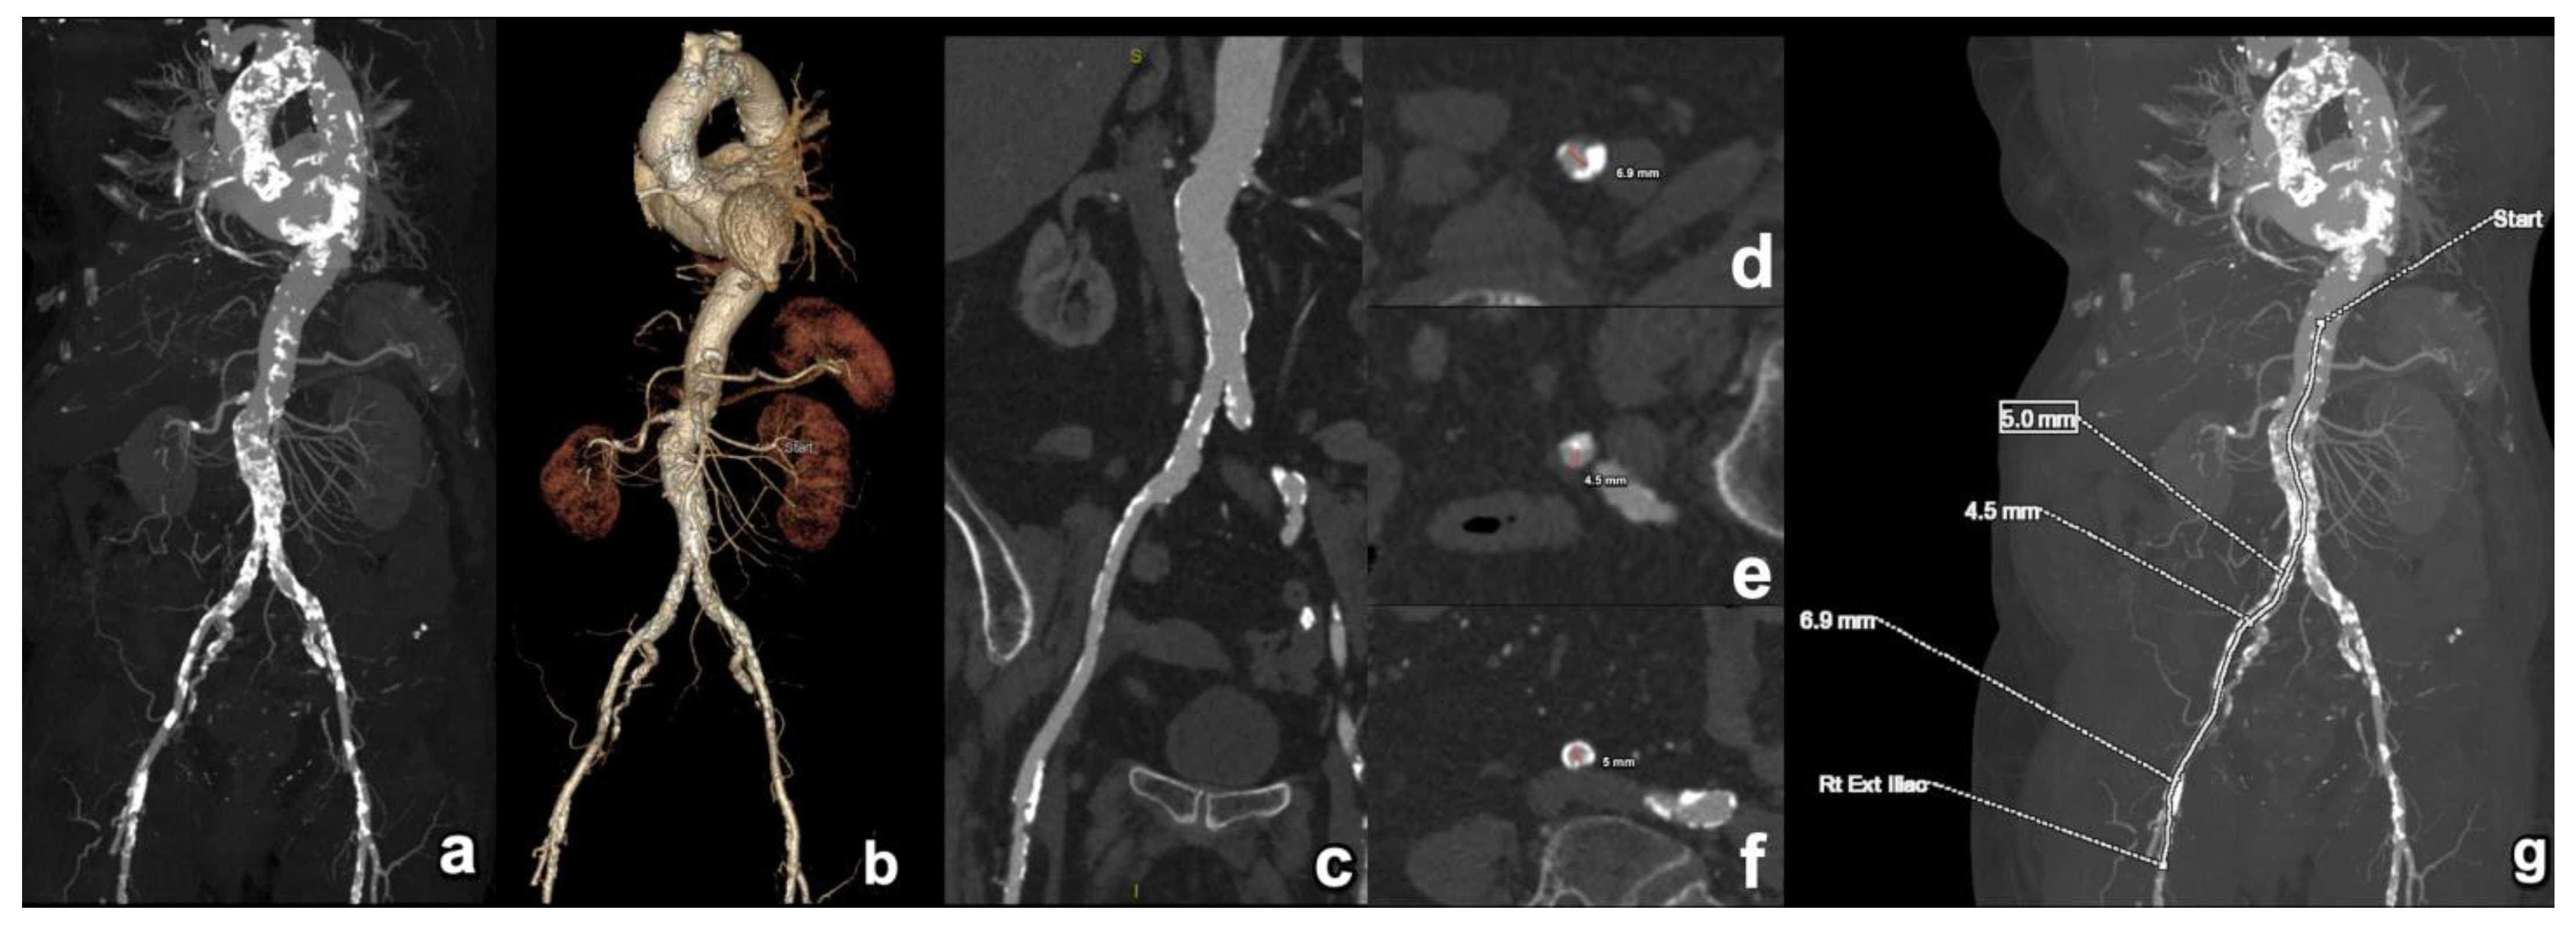

| Peripheral access vessel diameters | Minimal luminal diameters of the iliofemoral arteries | A minimal luminal diameter of 5–6 mm is generally required, depending on the delivery system. |

| Transfemoral | Most common and preferred approach. Access is typically through the femoral artery. | Least invasive. Preferred when feasible. | Requires an adequate iliofemoral vessel size and a lack of severe tortuosity/calcification. |